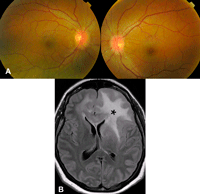

Figura 5. Papiledema atrófico, fondo de ojo: Se aprecian unos discos con márgenes borrosos y palidez difusa. Hay fenómenos de gliosis de los vasos peripapilares.

Figura 6. Papiledema incipiente. Paciente de 40 años con una lesión intracraneal, no presentaba afectación de la agudeza visual, ni discromatopsia, ni alteraciones en el estudio del campo visual. Figura 6A. Fondo de ojo: Se observaba una leve elevación de los discos ópticos en ambos ojos y no había delimitación clara de sus márgenes. Figura 6B. Resonancia magnética cerebral, corte axial T1: La lesión se localizaba en la región fronto-temporal izquierda, se extiendía al cuerpo calloso y a la región frontal izquierda. Provocaba obliteración de las cisternas pre-pedunculares e impronta de las amígdalas cerebelosas en el foramen magno. Estos hallazgos son sugestivos de hipertensión intracraneal.

Figura 7. Retinopatía óptica paraneoplásica. Una paciente con antecedentes de neoplasia de mama consultó por marcada pérdida visual bilateral subaguda y fotopsias. La detección de anticuerpos anti-recoverina confirmó el diagnóstico de CAR. Figura 4A. Fondo de ojo: Se aprecia una discreta palidez papilar y atenuación vascular. Figura 4B. Estudio electroretinografía convencional. Hay abolición de la respuesta de los fotorreceptores.